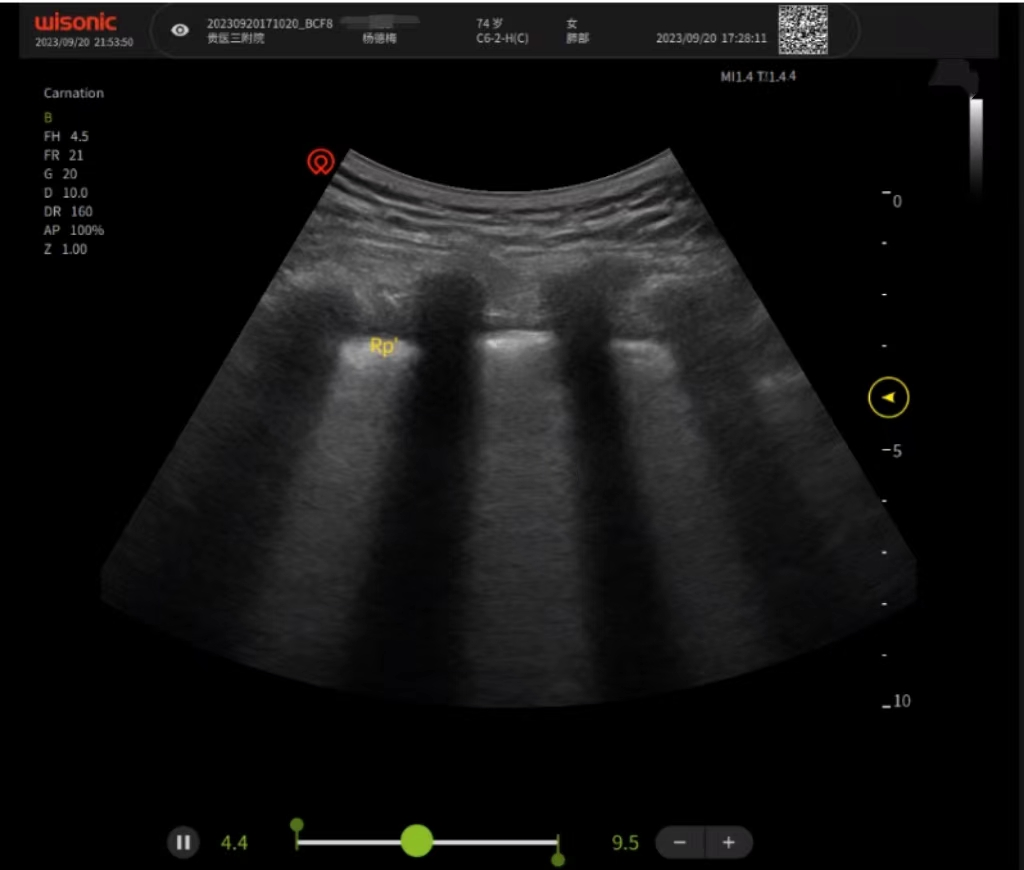

肺部超声

肺部超声可以在床边进行操作,是一种没有辐射、没有创伤,且不要求患者憋气的检查方法。可以多方位、多角度实时动态反复检查,进而在超声机上呈现不同的图像。通过分析,对疾病做出判断。对需要监护的病人来说,非常便捷,可以实时观察、对比治疗效果,提高了重症患者的救治水平和护理能力。

治疗前肺部超声